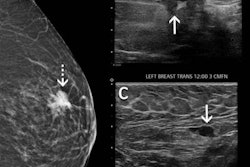

Noguchi et al explored the issue using data from the BreastScreen Western Australia (BSWA) program. Here, mammography screenings in women aged 40 years or older were collected between July 2007 and June 2017. These women were eligible for free mammograms every two years in the program. The data included 1,026,137 mammography screening episodes in 323,082 women.

The researchers found that 2,347 (40.9%) of the 566,948 screening exams in women with no recorded risk factors were positive for breast cancer. They also found that the cancer detection rate and interval cancer rate were lower than screening exams with at least one risk factor.